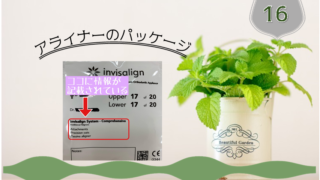

定期チェックアライナー#20 20/20(2nd)2クール目が終わり 今回は新しいアライナー作成のため再度スキャンする予定です。問題なく20枚終わることができました。3か月ぶりの定期チェックさて3か月ぶりの定期チェックです。マウスピース矯正...

歯列矯正  インビザライン

インビザライン  歯列矯正

歯列矯正  インビザライン

インビザライン  歯列矯正